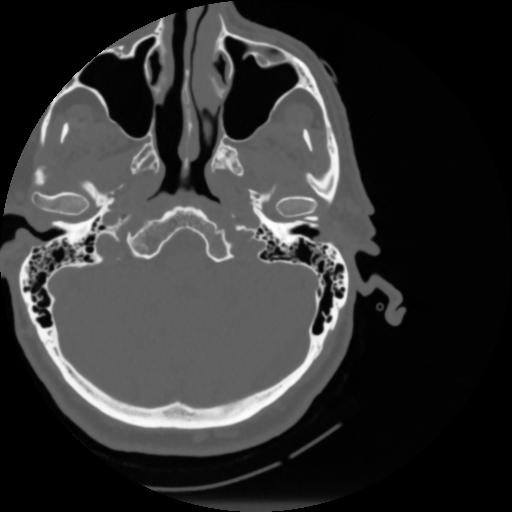

4 CEREBRO,,Vol,0.5,CEREBRO,,